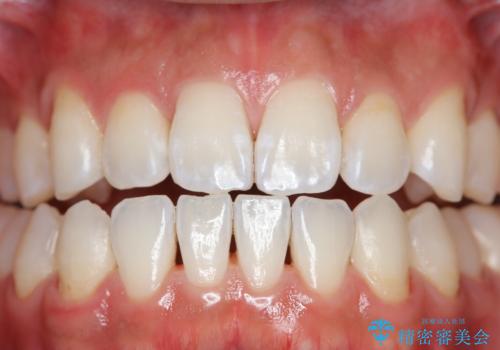

- コーヒーを毎日飲むため、歯が黒くなり気になるとのことでした。

エアフローワンは、特殊なパウダーを混ぜた水を水面にジェット噴射することでバイオフィルム(プラーク)・ステイン(着色)・早期歯石を天然歯やインプラント周囲から除去することが可能な歯面清掃器具です。

従来の荒い研磨剤などを用いた歯面への負担が大きいクリーニングとは異なり、歯質の負担を最小限にした歯面清掃と歯周ポケット内のメンテナンスを行えます。